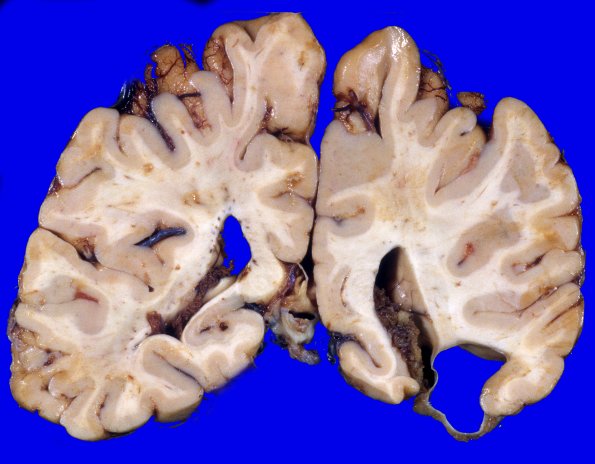

11A5 The arachnoid cyst does not communicate with the right lateral ventricle which is expanded, likely the result of ex vacuo change.